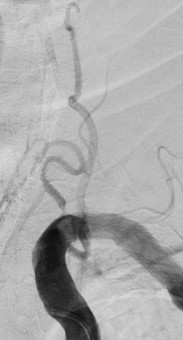

13:00 Больной подан в рентгеноперационную, выполнена церебральная ангиография: Ангиографические признаки атеросклеротического процесса брахиоцефальных артерий, тромботической окклюзии правой ВСА(Рис1), окклюзия левых ВСА(Рис3) и ПА(Рис2).

рис. 1 рис. 2